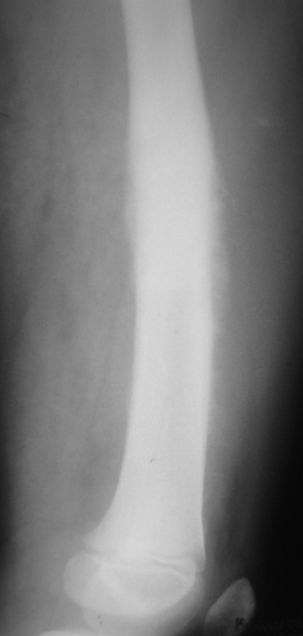

Мальчик 8 лет. Жалобы на боли в левом бедре. Со слов мальчика, ударился бедром несколько

недель назад, после чего и начались боли.

В общем-то, диагноз сомнения не вызывает злокачественная опухоль, вероятнее всего -

остеогенная саркома. У нас возникла дискуссия по поводу того, нужно ли брать открытую

биопсию для гистологического подтверждения диагноза, либо сразу направить ребёнка в

специализированный центр. С одной стороны, диагноз должен быть подтверждён

гистологически. С другой - каждое нерадикальное вмешетельство на опухоли увеличивает

вероятность метастазирования. В литературе чаще встречается такой подход - пациента сразу

направляют в специализированный центр, где ему проводят как биопсию, так и дальнейшее

лечение. Хотелось бы узнать мнение уважаемых коллег.